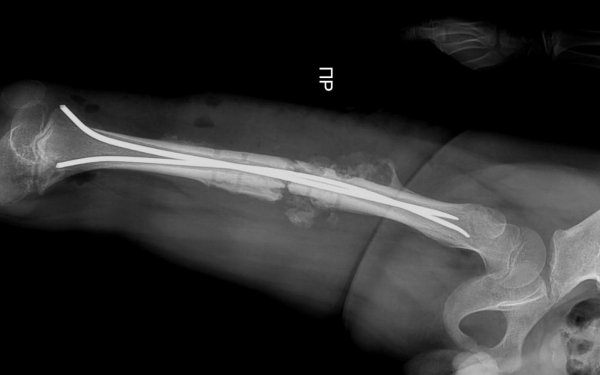

Гибкие фиксирующие стержни установили врачи юному жителю Актау

В стенах областной детской больницы впервые была проведена операция по установке гибких фиксирующих стержней, рассказал актауский общественник Азамат Сарсенбаев.

В течение часа детский хирург Курман Кайранов успешно заменил металлический на более современный гибкий стержень.

- Преимущество гибкого стержня заключается в том, что теперь при переломах больше не требуется делать большие разрезы в конечностях для установки фиксирующих стержней. Достаточно лишь сделать разрез в один сантиметр и вводить гибкий стержень под рентгеновским контролем, - рассказал Курман Кайранов.